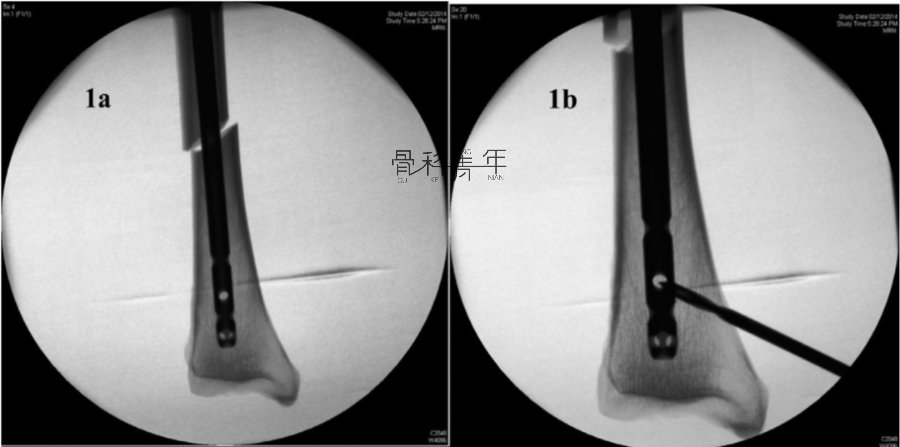

病例示例1:

1a-1b:胫骨中段骨折采用髓内钉固定。可见置入主钉后骨折对线不良,存在侧方移位及成角畸形。